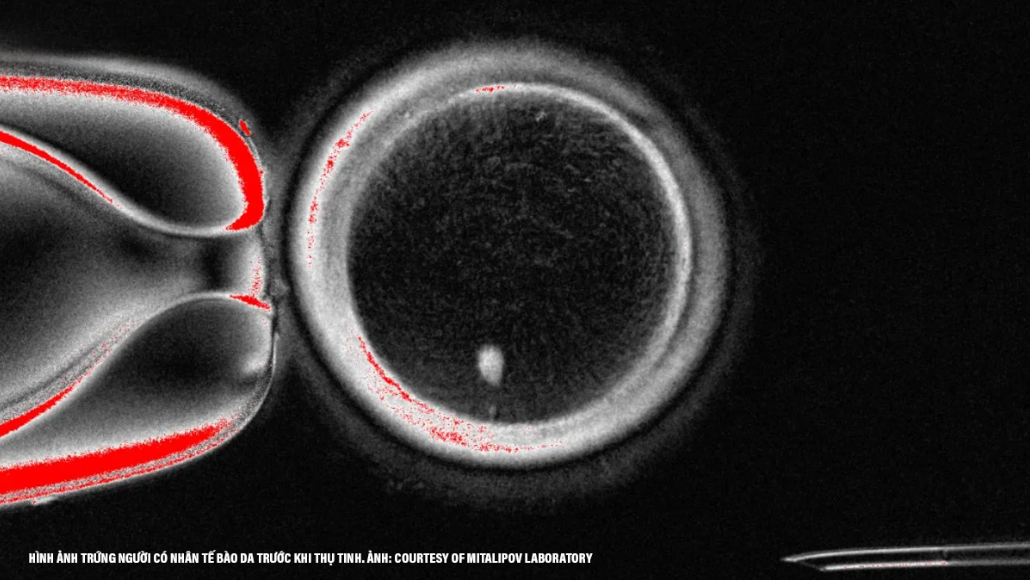

Trong cuộc thí nghiệm, nhóm đã lấy nhân của tế bào da người và cấy vào một trứng được hiến tặng đã loại bỏ ra nhân. Kỹ thuật này gợi nhớ đến phương pháp từng tạo ra con cừu Dolly nổi tiếng hồi năm 1997. Sau đó, trứng được kích thích qua xung điện và thuốc để bắt chước quá trình cho giảm phân, nhằm loại bỏ bớt bộ nhiễm sắc thể. Kết quả, họ đã thu thập được 82 trứng có thể cho thụ tinh.

(Minh họa)